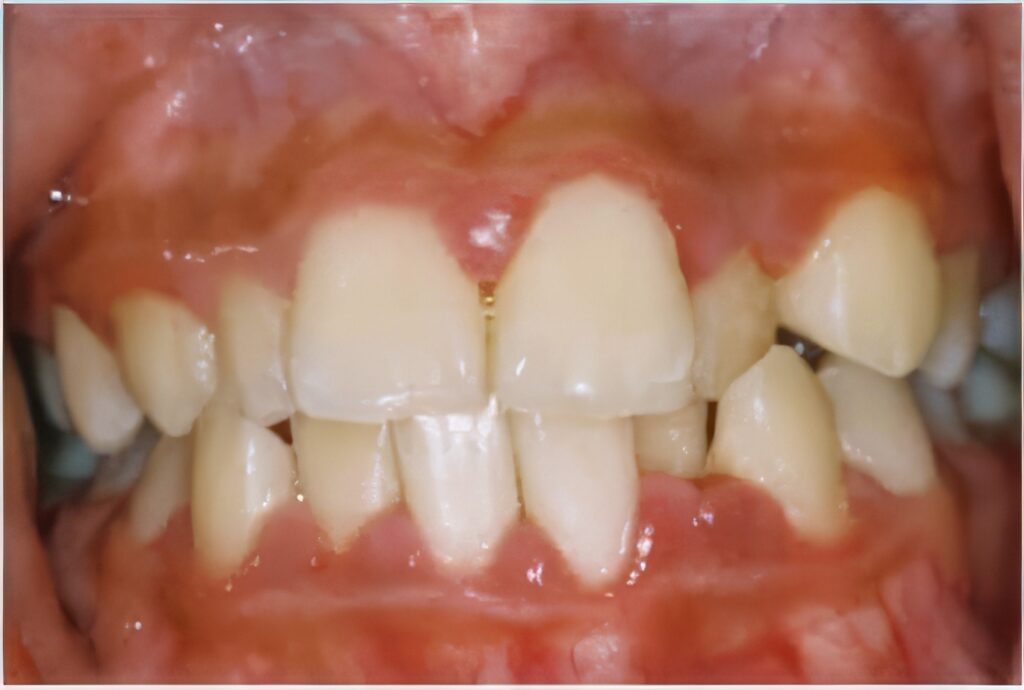

Gingivitis is likely the most common and well-known gum disease and is caused by excessive buildup of plaque and tartar. Gums will be highly sensitive in people with gingivitis and are likely to be red, swollen, and bleed when touched. Gingivitis is easily treated by improving your oral hygiene and going to the dentist for regular checkups and cleanings.

If gingivitis goes untreated it can cause a disease called periodontitis. This causes the gums to pull away from the teeth and form infected pockets around the teeth. This can lead to teeth and jaw bone damage quickly as your body tries to stop the bacterial infection, and without treatment periodontitis can lead to bone and the loss of teeth.